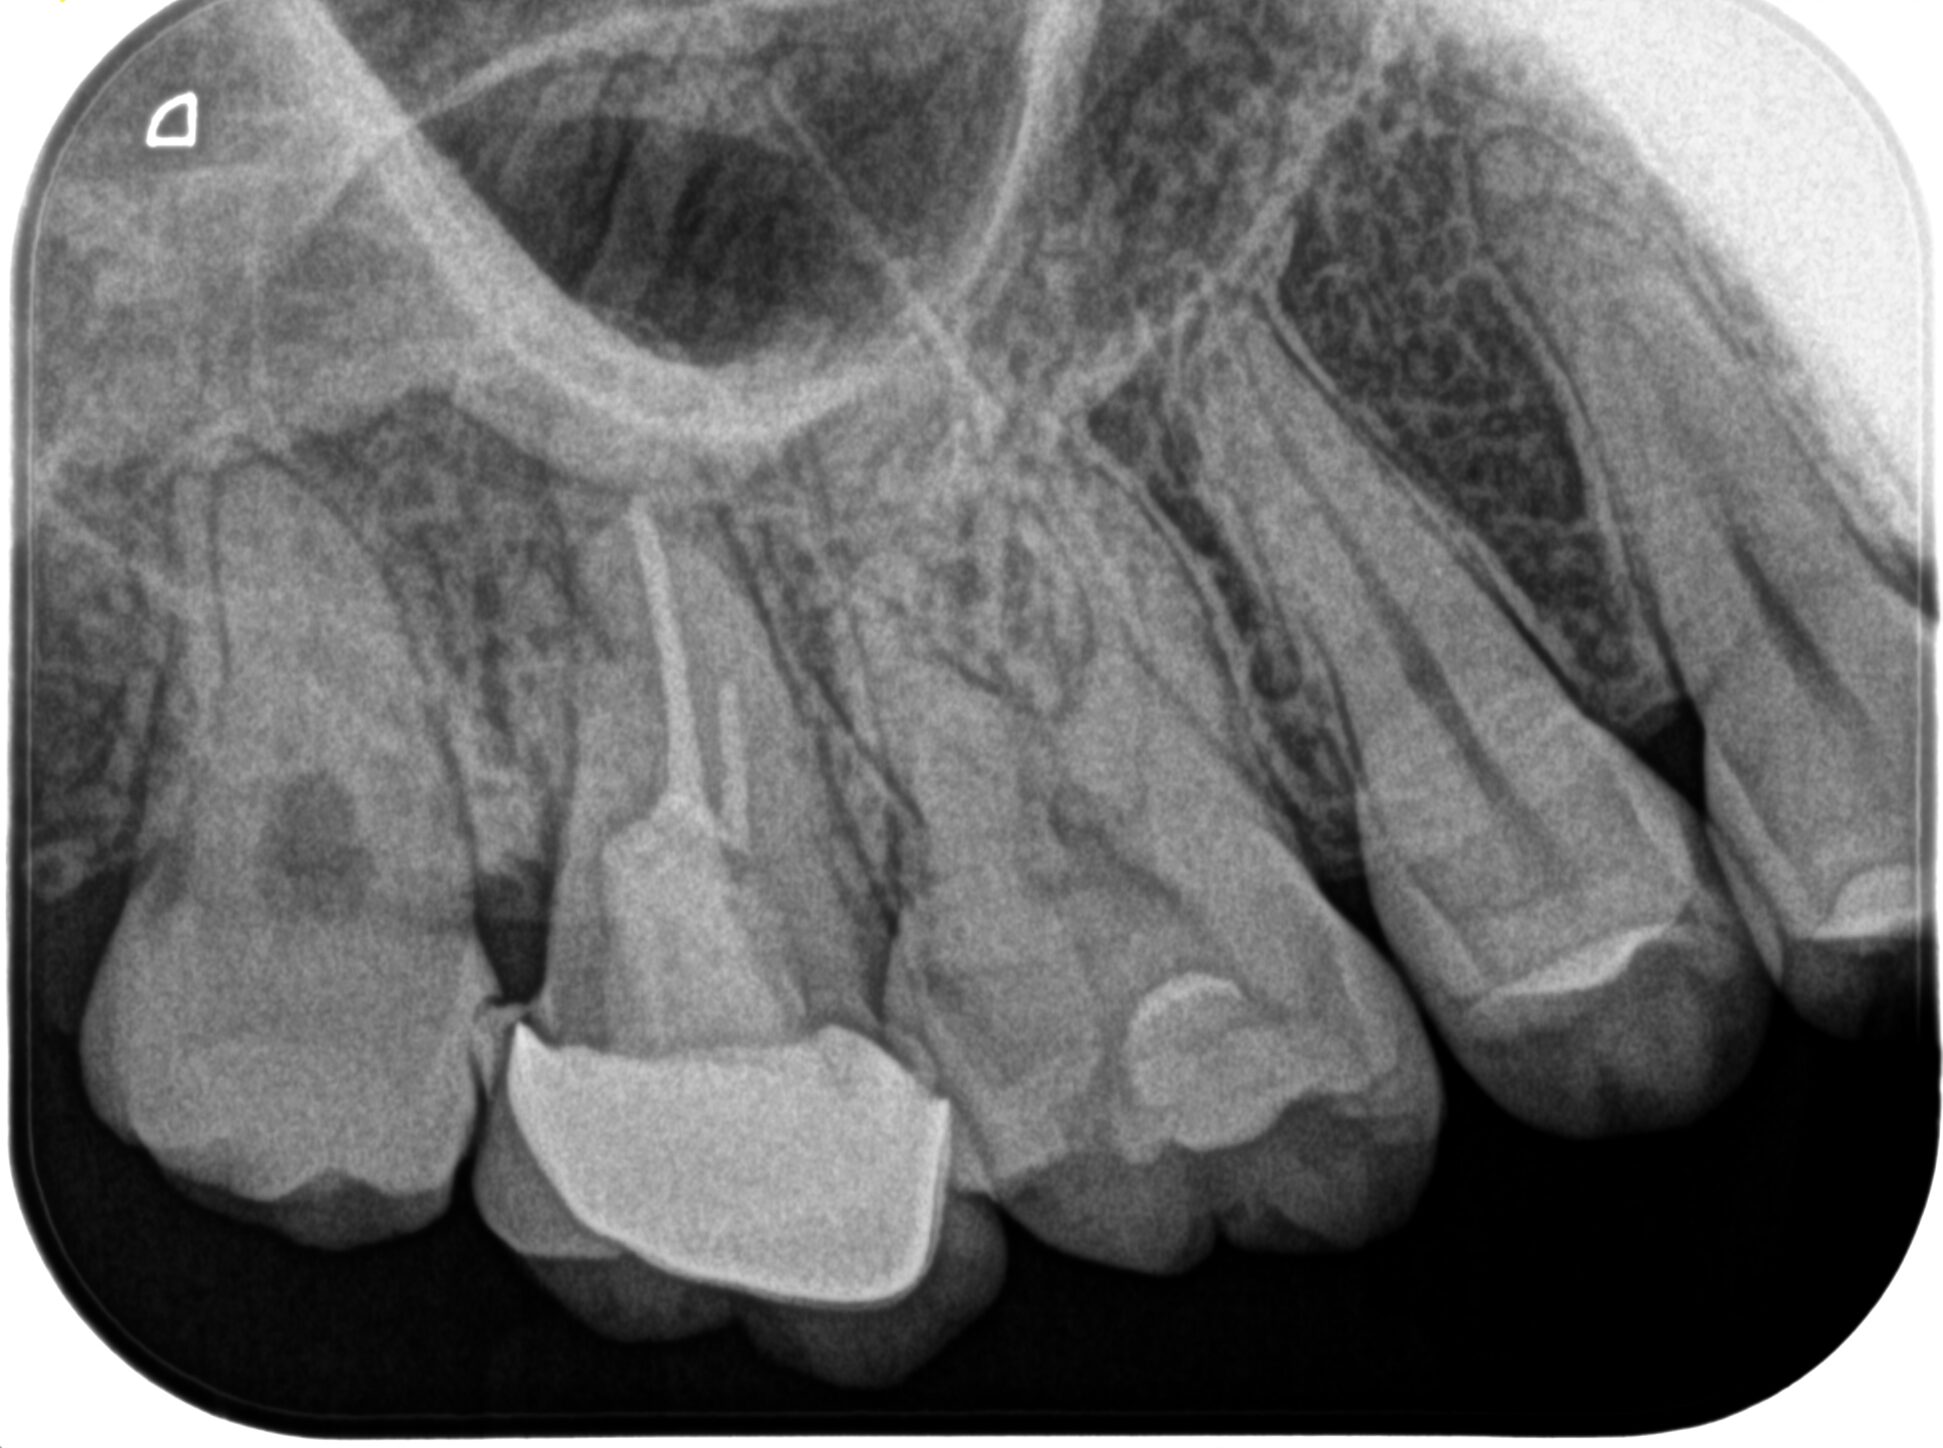

術後にPAを撮影した。

MB

DB

P

B

問題はないだろう。

逆根管充填の状態をイマイチ智度確認した。

MBをもう少し頬側方向に逆根管形成を広げた方がいいのだろうか?と疑問を持ったからだ。

が、

メチレンブルーが染まった場所を私は信じることにした。